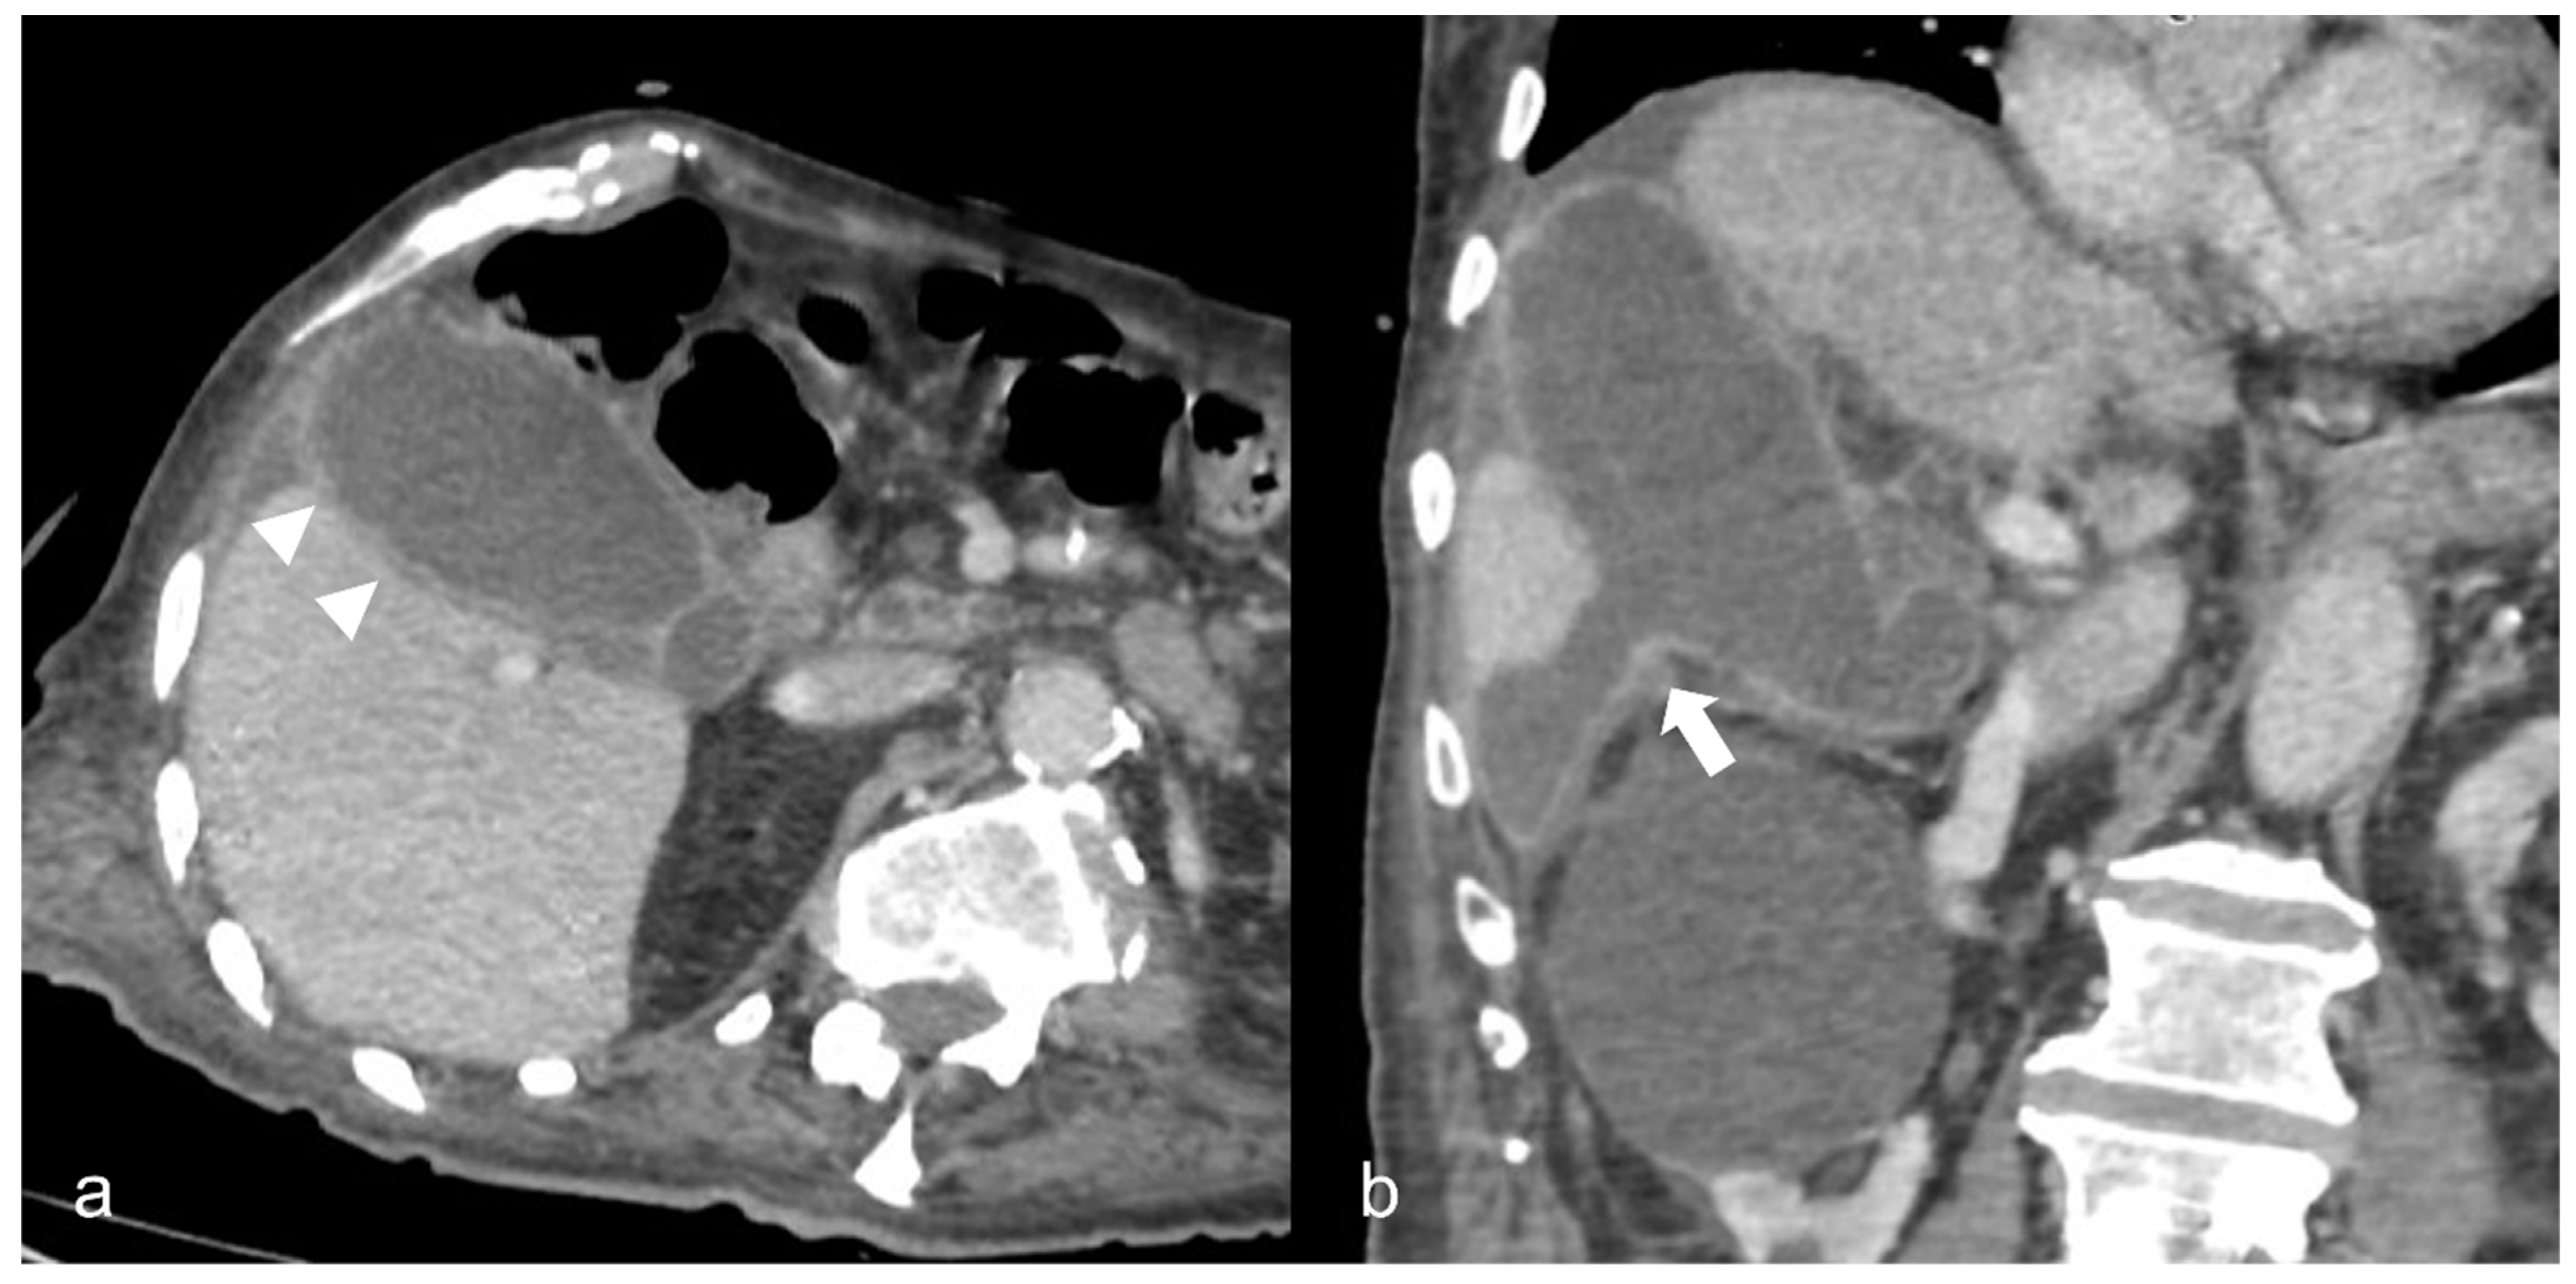

Figure 8. A 90-year-old COVID-19 patient presented acute right quadrant abdominal pain and cholestasis. Computed tomography on the axial (a) and coronal (b) plane showed acute cholecystitis with diffuse thickening of the gallbladder wall and pericholecystic fluid (arrowheads). Disruption of the gallbladder wall (arrow) is also present with fluid collection around the liver indicating perforation.